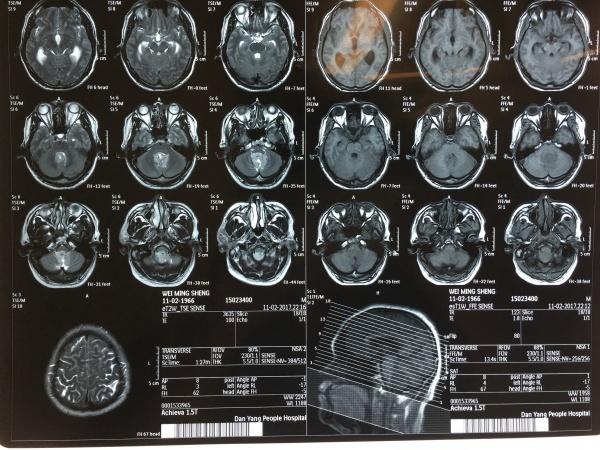

患者中年男性,主诉很是简单,头痛、头晕2月,近期有加重,在外院神内就诊,发现问题后,即刻转至我院,再行头颅MRI检查示:

术前我们考虑手术的难度共有以下几点:1、肿瘤广泛,四脑室、CP角、小脑蚓部、小脑扁桃体均有侵犯。2、需要打开四脑室,全切或次全切肿瘤。3、肿瘤与延髓紧贴,是否有明确间隙,如没有,是否处理延髓上的肿瘤。4、肿瘤范围广,可能肿瘤中已包绕了重要的血管、神经。